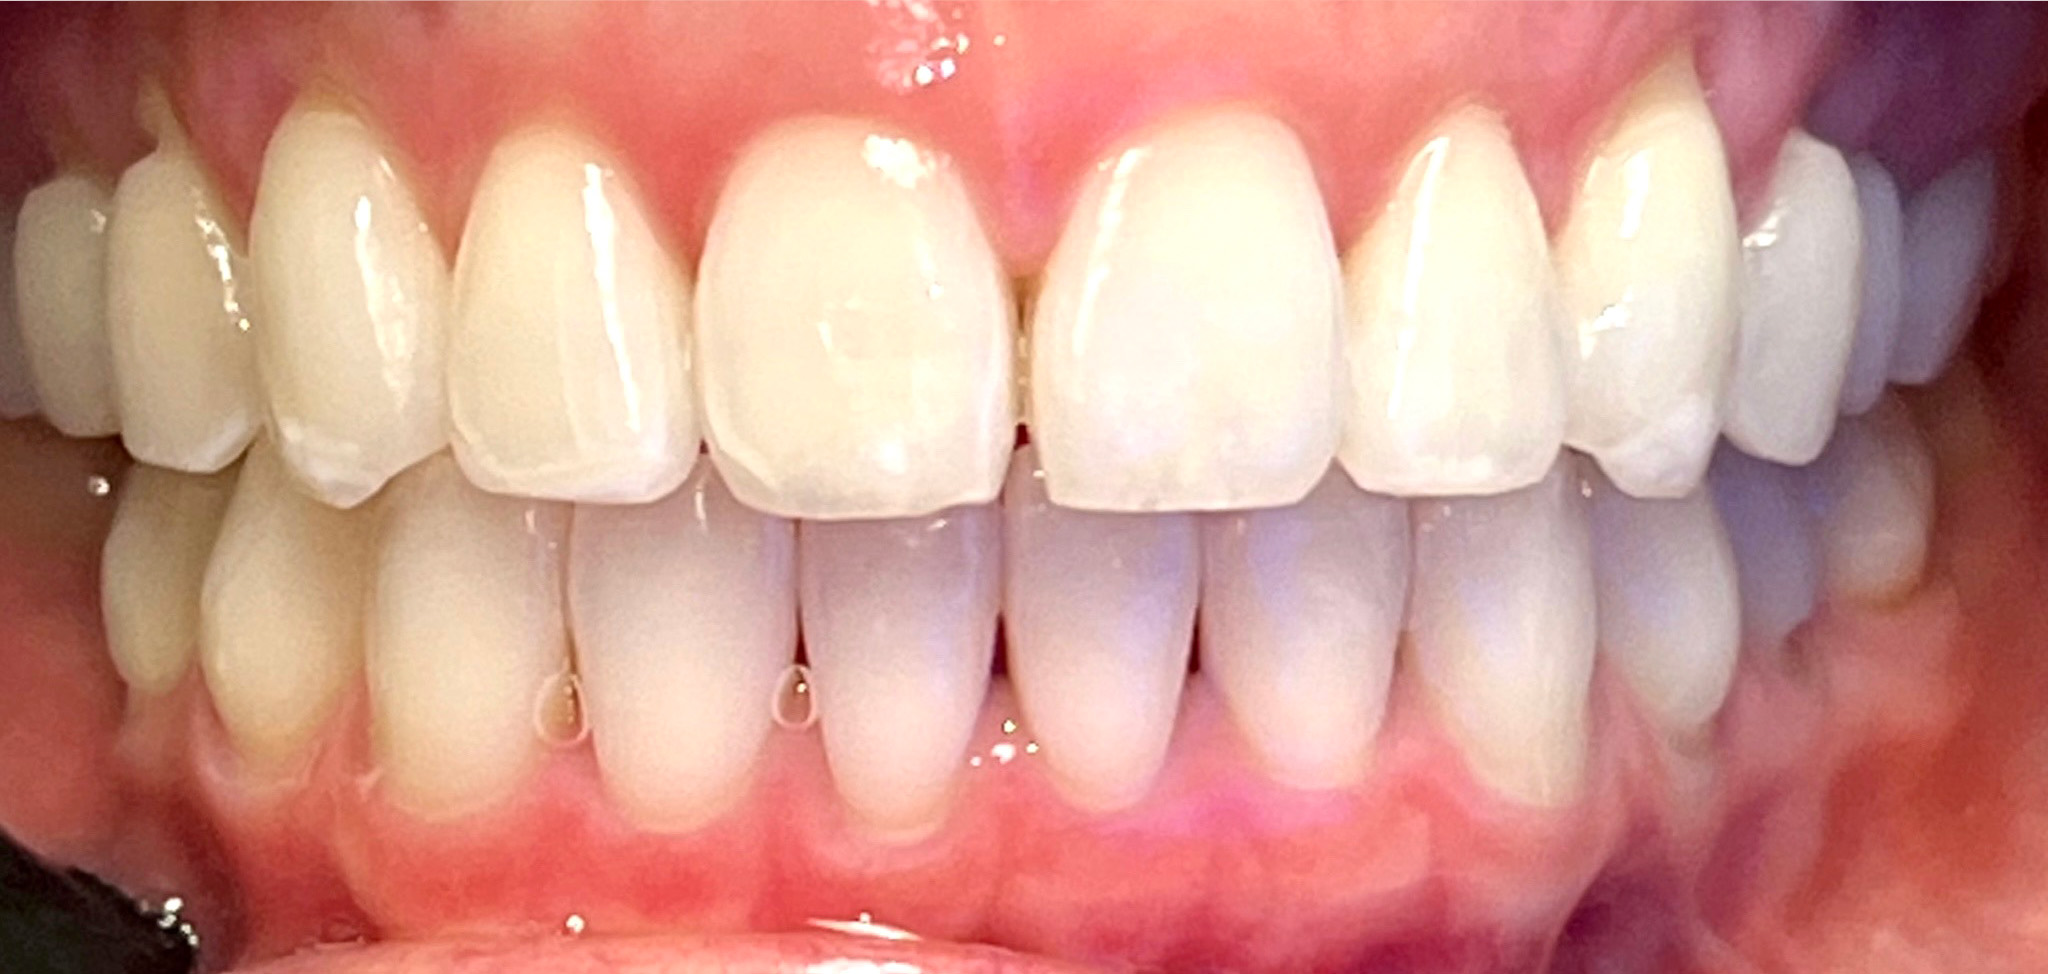

At Gramercy Smiles we are dedicated to creating lasting smiles through comprehensive care using the latest technology. We proudly offer personalized, patient-driven care focused on the health, beauty, and functionality of your teeth. Please browse our smile gallery below and contact us to schedule a smile consultation today.